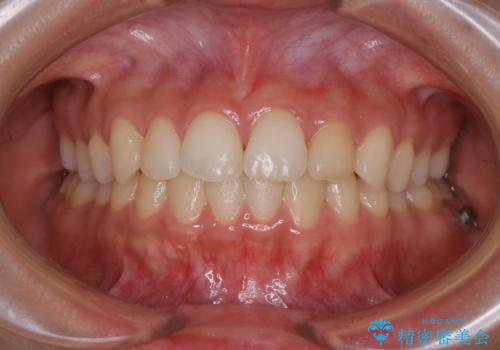

成人式の前撮り前に歯をきれいにしたい 初めてのPMTC